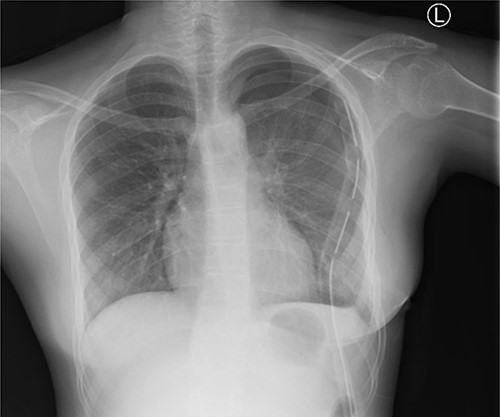

Post-operatively, the patient was monitored in ICU and kept on parenteral ceftriaxone 1 g and gentamicin 80 mg 12-hourly, paracetamol 1 g 8-hourly and pethidine 25 mg 6-hourly. She was extubated on post-operative Day 1 and transferred to general ward on the second day. The patient was discharged on 9th post-operative day. She was followed up at the surgical outpatient clinic at 2, 4 and 6 weeks post-operation where she reported full recovery and had normal findings on physical examination and chest X-ray (Fig. 5).

Chest X-ray (PA) shows no mass in the left hemithorax after thoracotomy and tumor resection; chest tube in situ; heart and lungs appear normal.